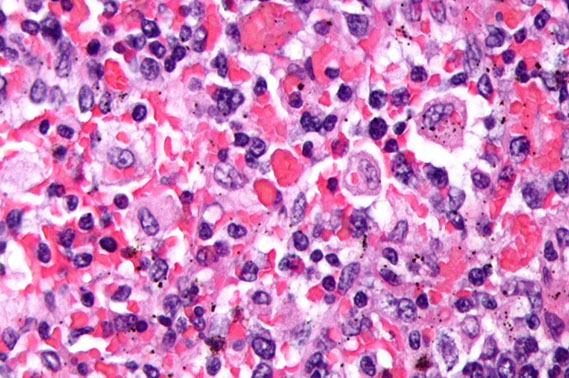

Hemophagocytic lymphohistiocytosis (HLH)

-aka macrophage activation syndrome or hemophagocytic syndrome [9]

Caused by systemic activation of macrophages and CD8 Tc cells, and assoc c T-cell lymphomas esp subcutaneous panniculitis like T-cell lymphoma

- macrophages eat up progenitor cells in BM and other stuff in peripheral tissues and release inflammatory mediators (TNFa, IL-6/12) that causes systemic inflammation leading to cytopenias and sx that look like shock

Criteria (need 5 of 8):

Clinical: Fever, hepatosplenomegaly

Hematologic: Cytopenias (>=2 of 3), Hemophagocytosis

Serum values: Hypertriglyceridemia, Hypofibrinogenemia, Hyperferritinemia

Immunologic: Low or absent NK function, Elevated soluble CD25

Micro: bone marrow biopsies show histiocytic hyperplasia with marked hemophagocytosis

- findings are similar regardless of underlying cause

- look closely for underlying lymphoma in adults

Px: Fulminant clinical course, poor without treatment

Tx: immunosuppression and cytotoxic agents, sometimes may need bone marrow transplant

- without therapy, high mortality rate

Florid HLH [13]. Bone marrow aspirate with markedly increased histiocytes with prominent hemophagocytosis with ingestion of RBCs and neutrophils (usually it is not thils florid, will probably only see 1-2 histiocytes eating blood)